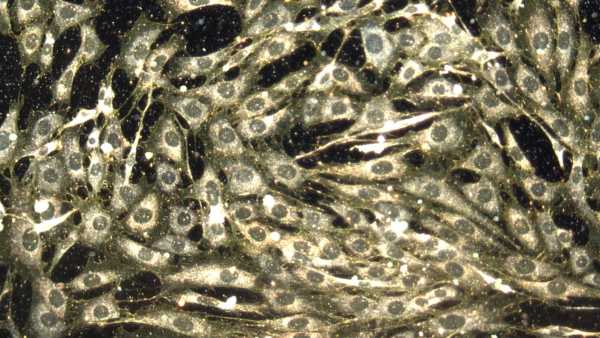

Нове дослідження показує, що тепер можливо розводити мишей із повністю розвиненою та функціональною імунною системою людини. (Зображення: Evgenyi_Eg via Getty Images)